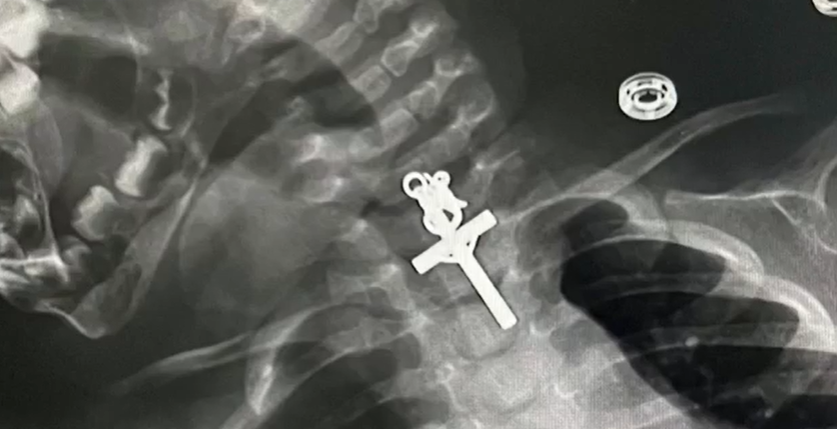

„Este un miracol”. Cum au reușit medicii să salveze o fetiță de zece luni, care a înghițit un crucifix. I s-a blocat în gât

O mamă s-a speriat de moarte după ce a aflat că fetița ei, în vârstă de zece luni, a înghițit un ...